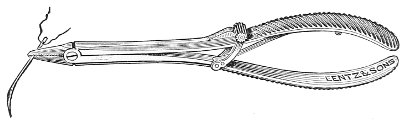

Fig. 4.—Double tenaculum.

The examination of the uterus and other pelvic structures is often facilitated by dragging the uterus downward with a tenaculum while the vaginal or the bimanual examination is being made. Sensation in the cervix is so slight that little or no pain is experienced in this procedure. The anterior or posterior lip of the cervix is caught with the single or the double tenaculum (Fig. 4), guided along the vaginal finger or introduced through the speculum, and the uterus is drawn down by an assistant in case the bimanual examination is being made, or by the external hand of the examiner in case a simple vaginal examination is made. When this is done the utero-sacral ligaments are made tense, and can be felt like two cords extending from the sides of the cervix outward and backward to the pelvic wall. The posterior surface of the uterus can be palpated often as high up as the fundus. The method is especially useful when the examination is made by the rectum, and in this way the whole posterior surface and the fundus of the uterus may be palpated (Fig. 5).

Fig. 5.—Bimanual examination with one finger in the rectum. The uterus is drawn down with the double tenaculum.